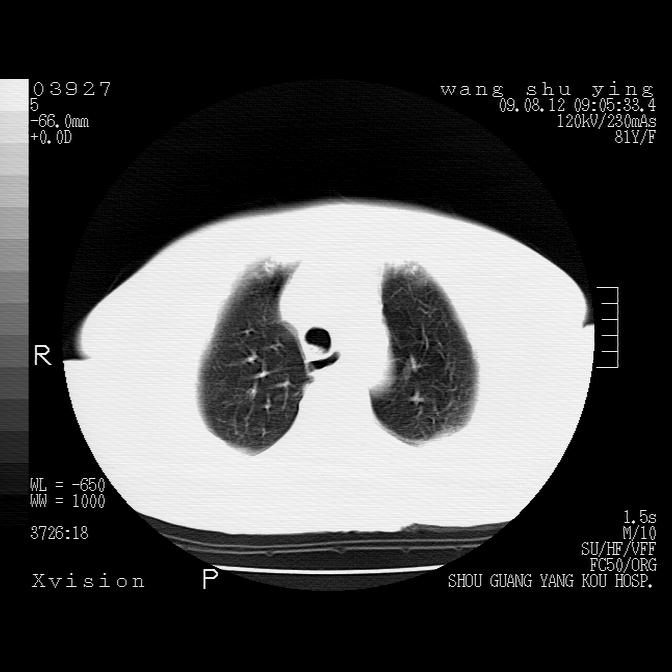

以下是引用帅河马在2009-8-12 12:59:00的发言:[br]两肺感染性病变伴双侧胸膜肥厚。[br]左侧甲状腺腺瘤不除外。[br]腹水+心包积液。[br][br][本贴已被 帅河马 于 2009-8-12 13:14:32 修改过]

以下是引用sdzyy在2009-8-12 18:17:00的发言:[br]两肺感染性病变伴双侧胸膜肥厚。[br]左侧甲状腺腺瘤不除外。[br]腹水+心包积液。[br]支持

以下是引用随光逐影在2009-8-12 19:42:00的发言:[br]1)两肺感染性病变伴双侧胸膜肥厚。2)不排除左侧甲状腺腺瘤。3)肝脏占位性病变;建议行进一步检查。